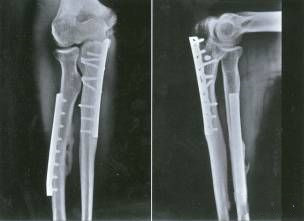

Le fixateur externe est considéré comme le premier choix pour un traitement précoce.

Support de gypse

Traction calcanéenne

Phase II : environ 2 semaines.

Il n'y avait pas d'infection systémique évidente ni de traumatisme aigu.

Pas de gonflement ni d'exsudation de la plaie.

L'ampoule est sèche, le gonflement diminue et les marqueurs osseux peuvent être touchés.

Peau ridée, des lignes de peau apparaissent.

Le résultat du traitement de la fracture de Pilon dépend de la qualité de la reconstruction articulaire et de l'état de la couverture des tissus mous.

Le meilleur moment pour la chirurgie dépend de l'état des tissus mous :

Stade précoce : l'opération a été réalisée en 6 ~ 8h, qui a duré 2 ~ 3h.

Délai : 7 ~ 10 jours, le gonflement a disparu et les rides de la peau sont apparues.

Quatre principes traditionnels qui doivent être suivis dans la reconstruction chirurgicale en un temps :

Reconstruction du péroné

Reconstruction de la surface articulaire tibiale

Greffe osseuse

Support de plaque osseuse